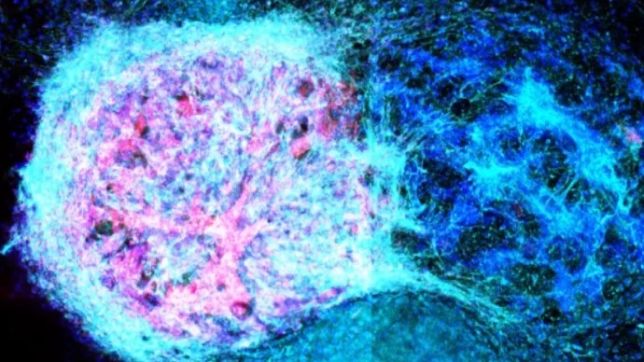

Os pesquisadores da Universidade de Oxford fabricaram um tecido cerebral de duas camadas por meio de impressões 3D de células-tronco neurais humanas. Os modelos foram implantados em cérebros de camundongos e demonstraram uma forte integração com o tecido dos animais.

A migração de neurônios entre o tecido hospedeiro e o implante foi vista como promissora pelos pesquisadores. As células implantadas também conseguiram se comunicar com as células dos camundongos.